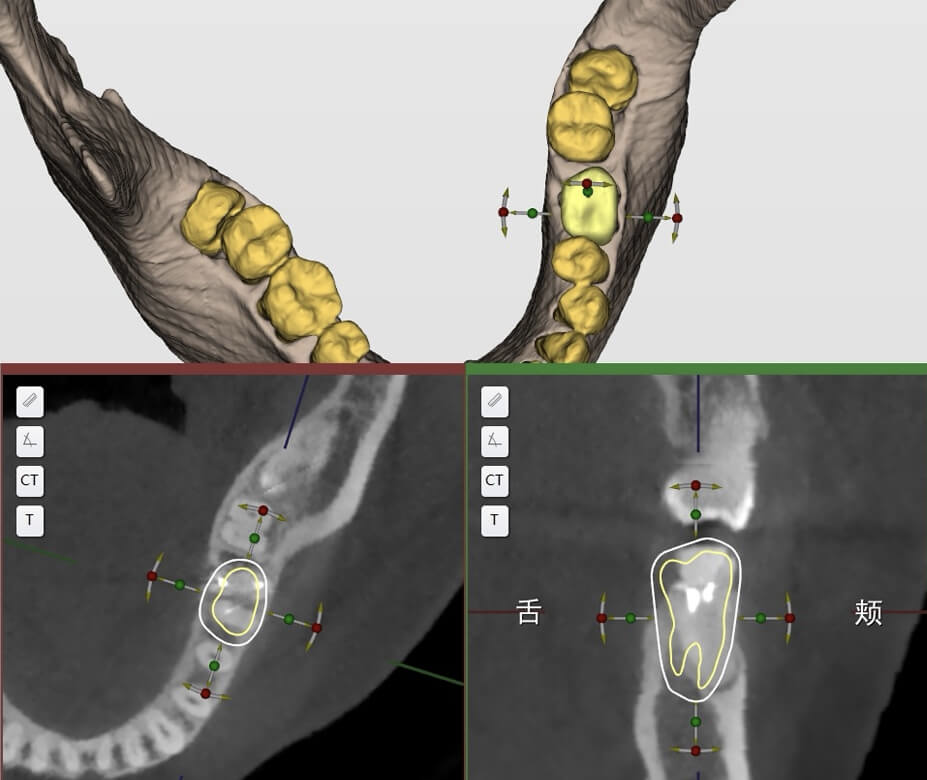

CBCT inicial + digitalização intraoral

Adaptação a diferentes dados de CBCT e digitalização intraoral; tratamento numa única visita, planeamento imediato; cirurgia no mesmo dia / prótese no mesmo dia

Exportação com um clique das principais estruturas anatómicas dentárias

Segmentação Inteligente Automática;

Extração Rápida de Informação sobre a Posição Dentária

Registo Secundário de Pontos e Nuvem

Integração precisa entre modelos virtuais e estruturas reais